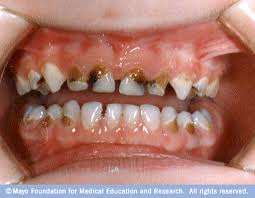

Có nhiều nguyên nhân dẫn đến tình trạng “sún răng”, nhưng nguyên nhân chủ yếu là do bé ăn quá nhiều đồ ngọt, các loại thức ăn có hàm lượng đường cao, tính bám dính mạnh nên dễ lên men sinh axit. Răng có hai lớp vỏ cứng từ ngoài vào trong theo thứ tự Men răng và Ngà răng. Lớp men răng và lớp ngà răng của răng sữa tương đối mỏng, độ canxi hóa thấp nên dễ bị sâu và khi đã bị sâu qua lớp men thì tốc độ bệnh tiến triển rất nhanh vì ngà răng kém cứng hơn men răng. Răng dần dần mủn và tiêu đi làm giảm thể tích thân răng, không đau nhức, chỗ bị sún chỉ nông chứ không sâu như lỗ răng sâu nhưng thường có diện tích rộng, màu đen hoặc nâu, đáy mềm ở những đợt tiến triển, lâu dần chỉ còn những mỏm răng gần tụt xuống lợi làm chân răng nằm sát với lợi.

Cũng có thể nguyên nhân do mẹ sử dụng các loại thuốc kháng sinh như Tetracycline, Doxycycline khi đang mang thai, làm cho răng bé phát triển không tốt, chất lượng men răng kém, độ cứng không cao, răng dễ bị tổn thương hơn nếu cùng chịu một tác động của yếu tố nguy cơ sâu răng, dễ bị sâu, mẻ, vỡ răng, men răng biến thành màu vàng sẫm.